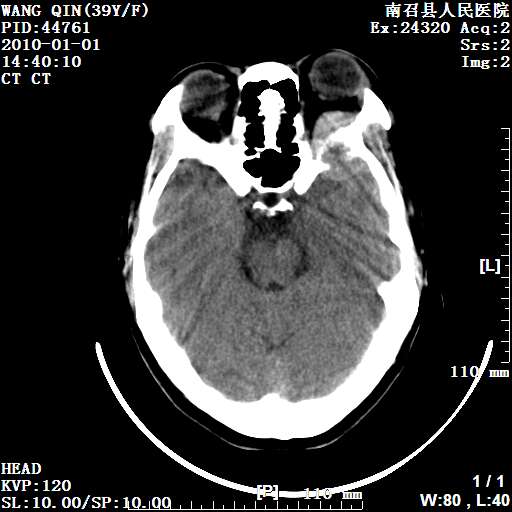

以下是引用随光逐影在2010-1-22 9:03:00的发言:[br]考虑左侧中颅窝(蝶骨翼区)脑膜瘤侵犯蝶骨翼并突入左侧眼眶。

以下是引用水过无痕在2010-1-22 14:55:00的发言:[br]一、定位:颅外占位;二、定性:恶性可能性大;三、组织来源:来源于左侧眼外直肌或其他部位;考虑为:横纹肌肉瘤>转移瘤>脑膜瘤.